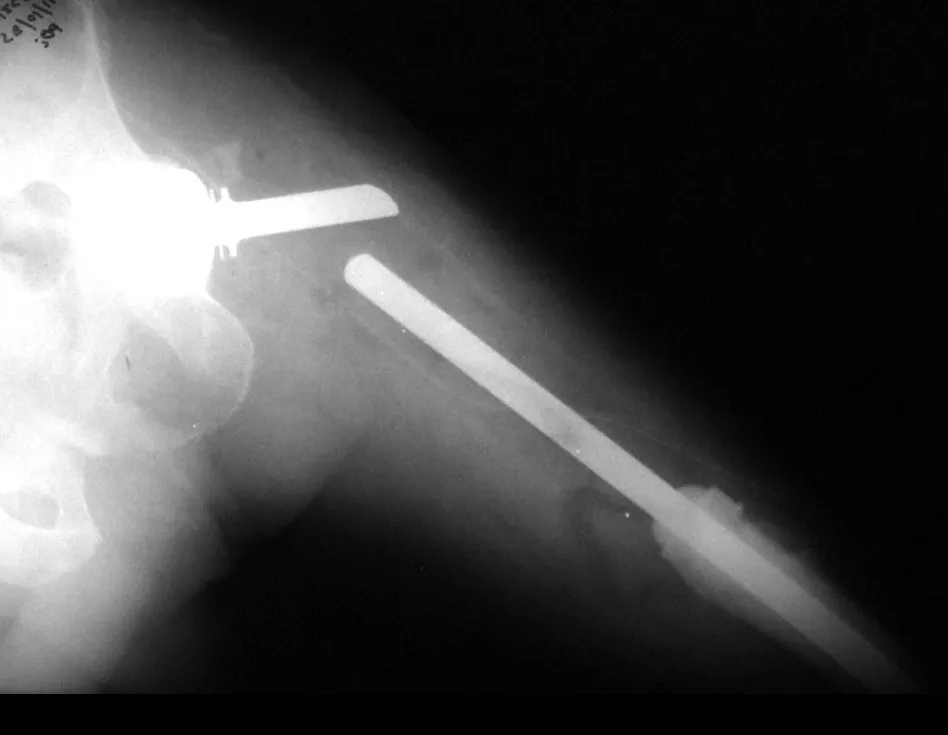

Fig. 3 – Após 8 meses da 1ª cirurgia – peças de aço inoxidável – encaixe da placa permitindo o deslizamento – RX após a 2ª cirurgia.

Fig. 3 – 8 months after the 1st surgery – stainless steel parts – plate fitting allowing sliding – RX after the 2nd surgery.

We are afraid to replace the stabilization method with external fixators, given its complications, both due to degenerative muscle injuries, trophic and functional changes they cause, and the risk of infection in patients undergoing chemotherapy. To resolve that situation, we requested the manufacture of a device consisting of two pieces of stainless steel that could be adapted to the proximal segment of the osteosynthesis, in order to maintain the support provided by the angled plate and at the same time allow it to slide and not block the bone growth (fig. 3). We performed a small medial surgical access, at the proximal end, removed the screws fixing the plate stem to the bone (directed from medial to lateral), and placed the curved blade between the femur and the plate, affixed the second blade shaped to adapt We placed it over the rod of the angled plate and screwed it in the anteroposterior direction (fig. 4).

In this way, we obtained good stability in the sense of blocking the efforts of rotational, varus, valgus, retrocurvatum or antecurvatum movements, but allowing the plate stem to slide as bone growth occurred (fig. 5).